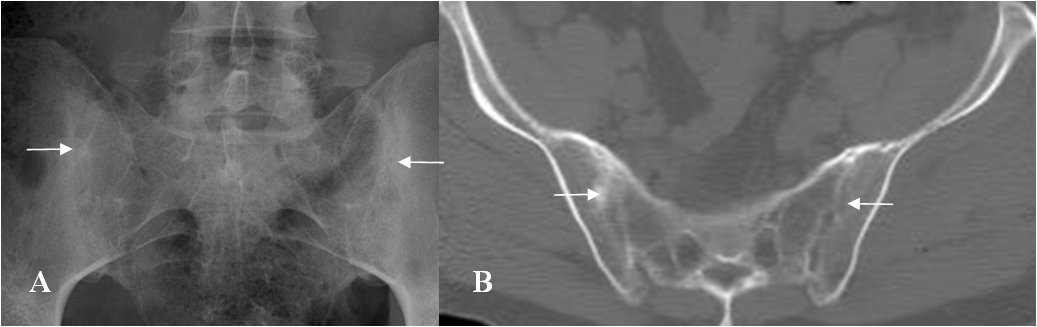

Fig 57 B. Espondilitis anquilosante.

A: Rx AP y B: TAC axial. Esclerosis y erosión de los componentes iliacos, de ambas articulaciones, por espondilitis anquilosante.

Fig 57 C. Espondilitis anquilosante.

A: Rx AP y B: TAC axial. Fusión de la articulación sacroiliaca derecha y disminución del espacio y esclerosis de la izquierda, por espondilitis anquilosante.